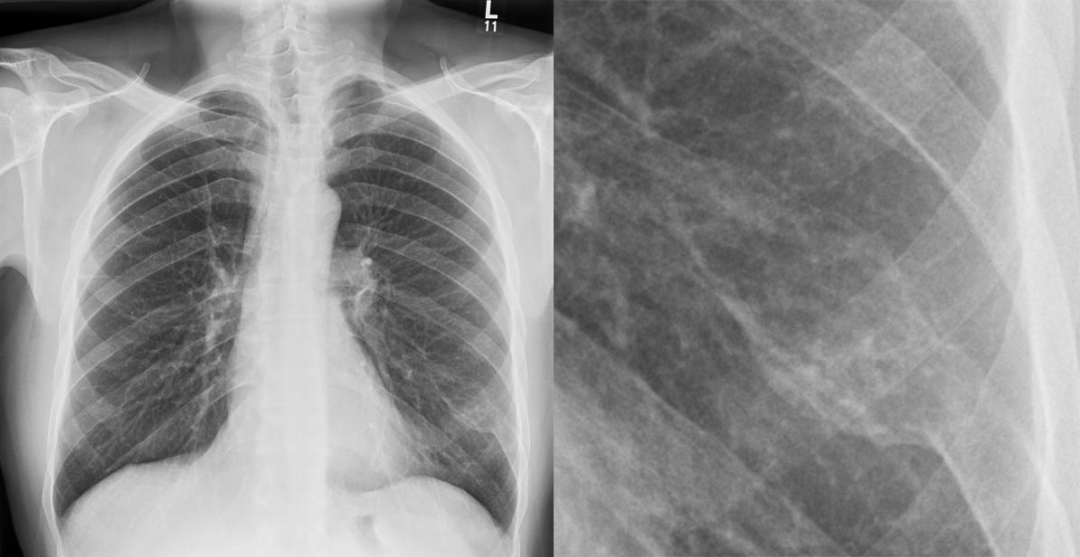

(注:左侧第 9 肋骨后段见囊状膨胀性透光区,边缘见硬化边,病变范围局限。)

(注:左侧股骨上段骨质呈 「 牧羊人拐杖 」 样改变,见囊状膨胀性透光区,边缘见硬化边,临近骨皮质变薄,病变范围较局限,伴左侧股骨上段畸形。)